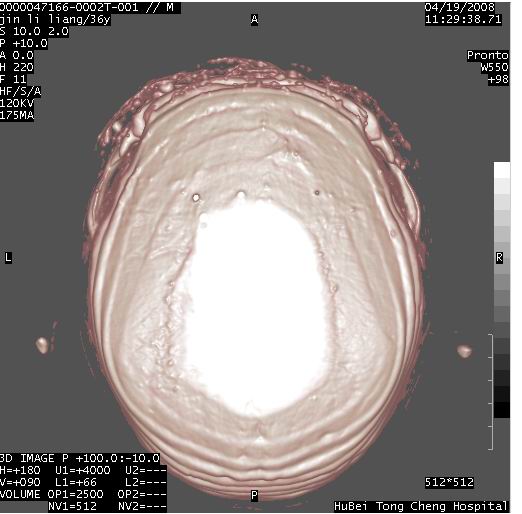

患者 男,36岁。头面部“土炮”炸伤。pe:面目全非,伤口流血不止。

临床诊断:头面部外伤。

颅脑ct轴位平扫(层厚、层距均为10mm),图像如下:

迎面一炮,满脸开曝。额顶部头皮及软组织挫伤并异物,左眼球破裂积气并异物,典型的面目全非,惨不忍睹。